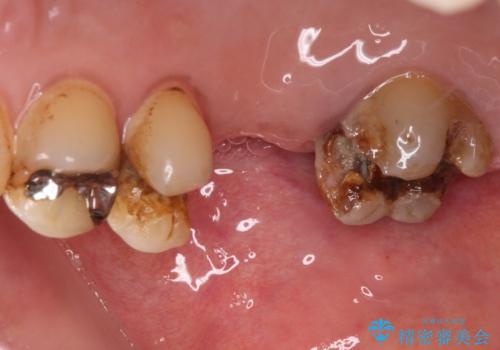

- 詰め物が外れたまま放置してしまったとのことで来院された患者様です。

詰め物が外れた部分は虫歯が進行しており、周辺には歯石が付着している状態でした。

1歯欠損していたため、オールセラミックブリッジによる補綴治療を行うこととしました。